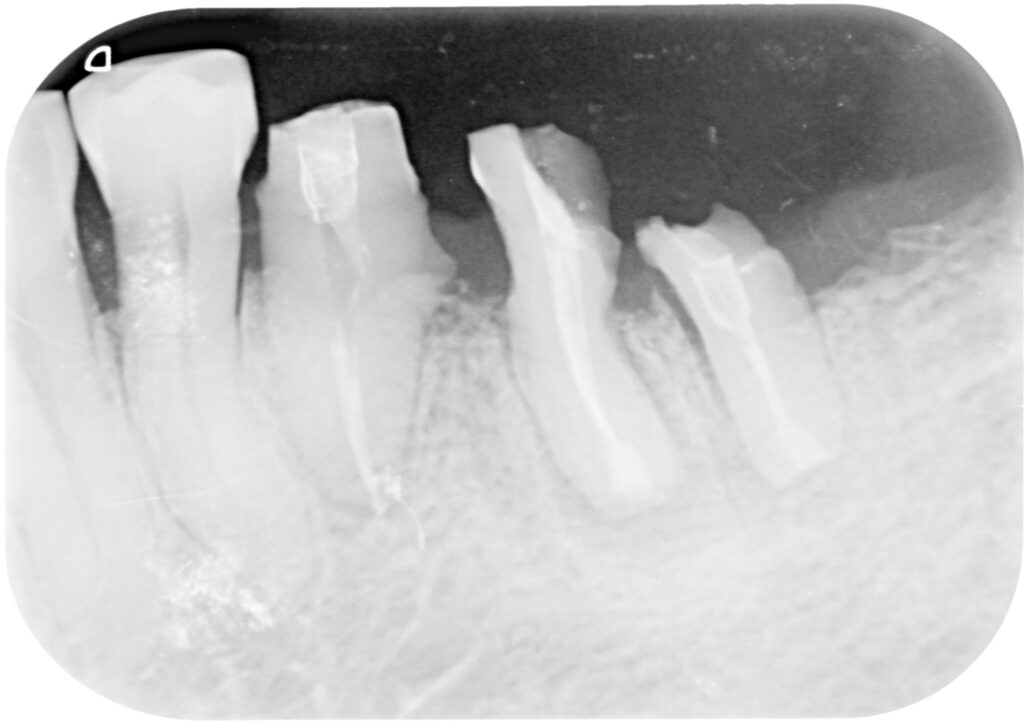

위 분은 2013년 항암치료 후 내원하셨는데요, 어금니가 아미 많이 상해 치아가 녹고 파인 상태였습니다. 발치 후 임플란트가 필요한 상황이었지만 여러 번의 권유에도 임플란트에 대한 거부감이 심해, 임플란트 치료가 불가능하였습니다.

하지만 틀니를 해야 할 정도로 이가 없지는 않아 재신경치료 후 36번 치아를 살려볼 계획을 세웠습니다.

재신경치료는 치아의 뿌리까지 연결 통로를 관통시켜주는 것이 중요한데, 현재 상황에서 불가능하여 뿌리 끝의 염증을 제거하기 위해 의도적재식술을 시행하였습니다. 시행 중 치아 뿌리가 분리되면서 큰 어금니 한 개가 작은 어금니 두개로 분리되었습니다.

맨 뒤 사랑니는 제거한 상태입니다. 자연치를 살리기 위한 방법으로는 재근관치료, 치근단 절제술, 의도적재식술, 치근 분리술, 치관 확장술, 포스트&코어가 있는데요, 하나의 치아를 위해 상기 치료가 모두 적용되었습니다.